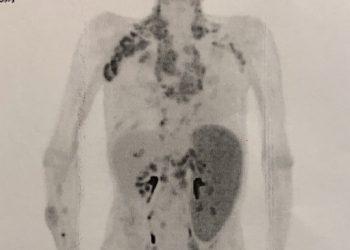

身上有硬塊不在意,竟是淋巴癌

年過70歲的德叔,長年體弱多病,因疲於出入醫院,便養成大病才找醫生,小病就自行處理的習慣。有次發現腋下有腫塊,並不以為意。過些時日脖子也長出硬塊,因沒什麼特別痛 ...